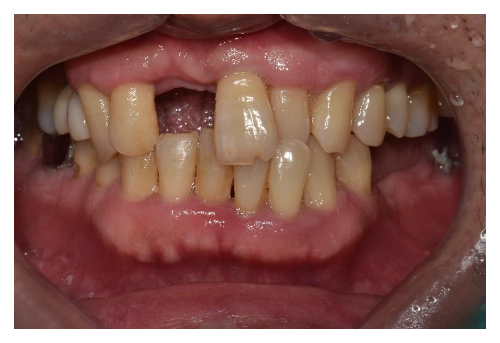

충치치료

1 치과공포증 치료 케이스

안녕하세요.대표원장 손승환 입니다.오랫만에 블로그 글로 인사드리는 것 같네요.요근래 환자분들이 많이 찾아주셔서 너무 정신없..